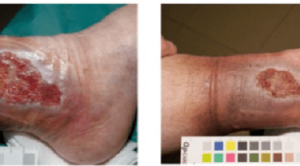

Efektivitas Madu sebagai Balutan Ulkus Diabetikum

Efektivitas madu sebagai balutan (wound dressing) ulkus diabetikum telah banyak diteliti, di mana hasi studi in vitro dan studi pada hewan menunjukkan...(Baca Selengkapnya)

Prinsip Penatalaksanaan Luka Kronik

Dalam penatalaksanaan luka kronik, berbagai faktor lokal maupun sistemik harus diperhatikan untuk membantu mencapai penyembuhan yang optimal. Luka kronik adalah luka yang...(Baca Selengkapnya)

Manfaat Terapi Oksigen Hiperbarik untuk Ulkus pada Kaki

Terapi oksigen hiperbarik dikembangkan untuk penyakit dekompresi, dan kemudian telah dilakukan uji coba untuk penanganan kondisi lain, termasuk ulkus kronis pada kaki....(Baca Selengkapnya)

Peran Nutrisi pada Penyembuhan Luka Ulkus Diabetik

Peran nutrisi pada penyembuhan luka ulkus diabetik masih menjadi topik yang hangat diantara klinisi. Ulkus diabetik pada umumnya memiliki angka kesembuhan yang...(Baca Selengkapnya)